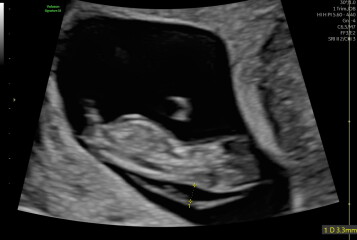

I went for what was meant to be a reassurance scan today at 10+2 weeks scan (I’ve had a scan at 6,8, 9 due to previous miscarriages and minor bleeding). What I was hoping would be a fun experience for my partner and I turned into us leaving sick with worry. The sonographer said the NT was thickened and there was a very large amount of fluid around the fetus’s head (4.7mm).

I’m preparing for the worst at my 12 week scan and test. I just wondered if anyone has had this level of fluid at 10weeks and it had cleared by the 12 week scan?

I really can’t remember now (15 years ago) but as I was racking my brains I realised it’s called cystic hygroma. I was sick to my stomach too. Literally thought of nothing else and if I’m honest didn’t believe them when they said all was fine at my next two scans because I kept thinking how could it be. But it was and I firmly believe that the scan is a snapshot of that day. Things change and in the nicest way, are the sonographers at the private place really experienced or are they literally looking at sexing and the rest is picked up knowledge? Go to your nhs appointment armed with all your questions and please look after yourself during the waiting time x